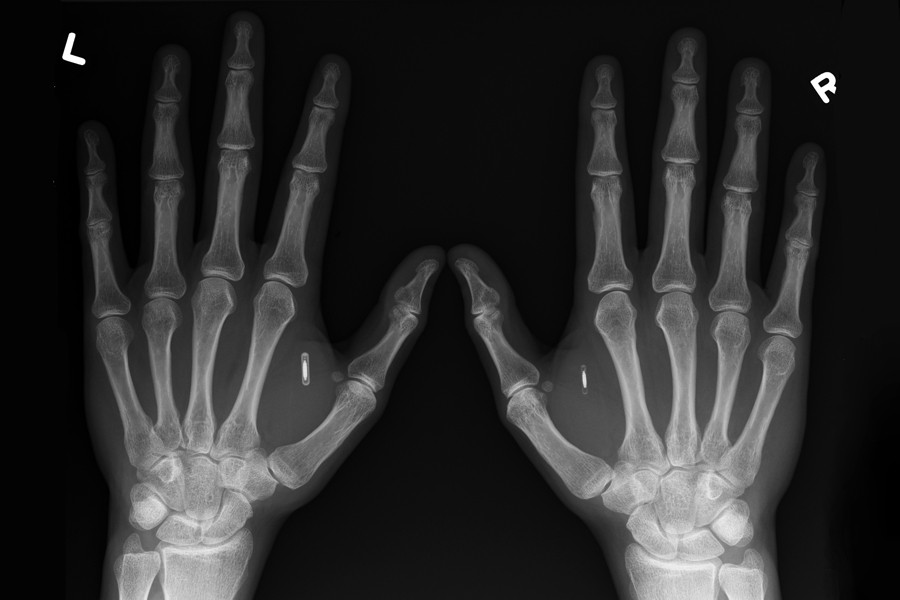

— Это устройство длиной 14 миллиметров с независимой памятью и небольшой антенной. Мой чип поддерживает два стандарта передачи данных — NFC и RFID. Заказал его на специализированном сайте. Комплект с чипом, шприцем, стерильными инструментами и материалами для проведения имплантации обошелся мне в $89,9.

— Нет, я обратился к мастеру в пирсинг-салон. Имплантировать решили в правую руку в тыльную сторону ладони между большим и указательным пальцами. Место выбрано не случайно. Эту часть руки сложнее всего травмировать при падении. В мировой практике это стандартное место для чипирования.

— Нет, они не магнитятся. Чип прозрачен для МРТ-аппаратов, виден только на рентгене. На него не реагируют даже рамки в аэропортах.